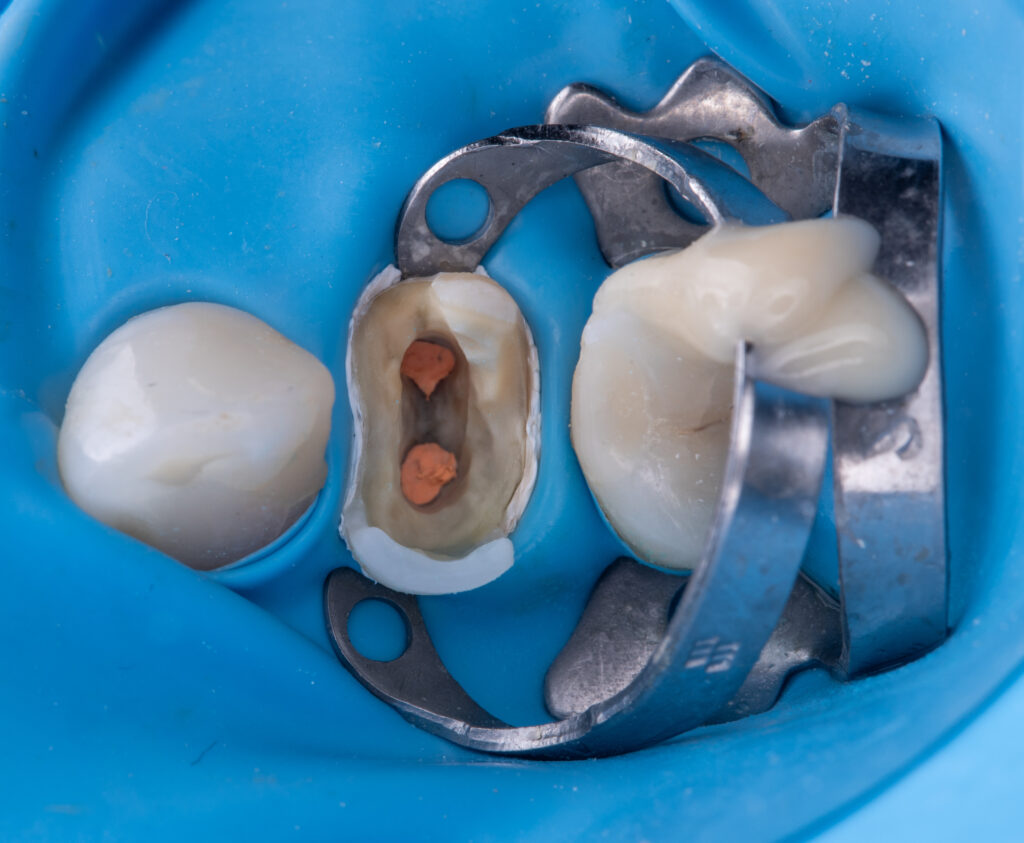

The first stage involved removal of the titanium post using two ultrasonic tips (applied from opposite sides of the tooth with water irrigation).

Next, de-obturation of the root canal system was performed, followed by negotiation of two previously missed sclerosed root canals using the Nick system and 5.25% sodium hypochlorite (a total of 25 ml of solution was used – 5 syringes of 5 ml each).